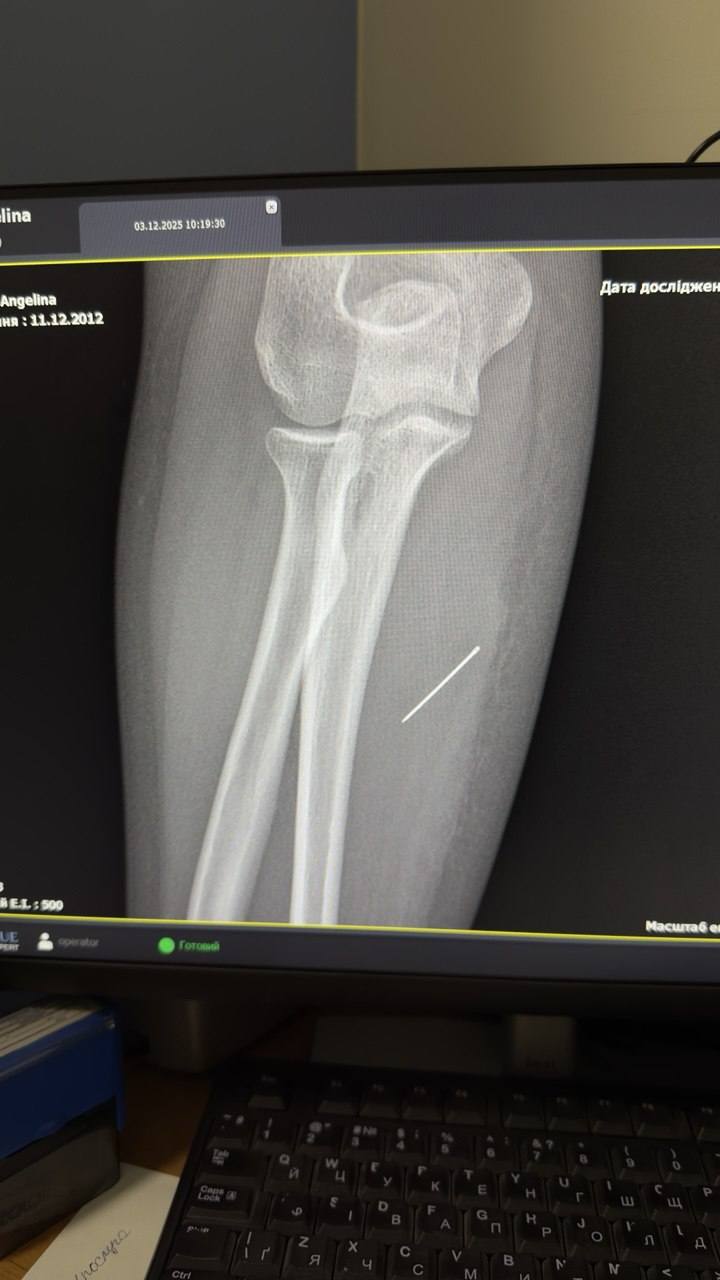

З’ясувалося, що коли Ангеліна збиралася до школи, застосовувались графіки відключень світла і вона не помітила на своєму столі голку після шиття, яку вона ненароком загнала собі в руку. Протягом тижня, поки школярка ходила з голкою в руці, вона просунулася глибше. На рентгені лікарі побачили, що голка зайшла в руку Ангеліни на 45 градусів та застрягла в м’язі.

Головною ціллю втручання було те, аби витягнути голку за траєкторією її входження, щоб вона не зламалася. Тому що потім шукати уламки голки в м’язах дуже складно. «За допомогою рентген-навігації ЕОП хірурги точно визначили місце знаходження стороннього тіла, невеликий розріз та правильно і безпечно його вилучили», – розповіли у лікарні.